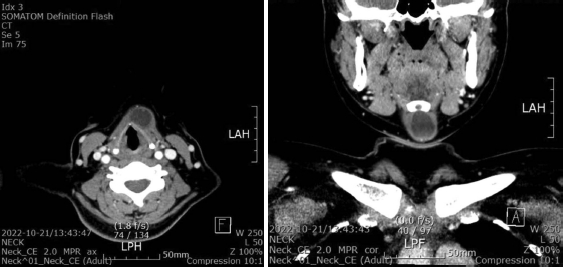

30세 여자 환자가 설골 직하방에 몇 일 전부터 종물이 촉진되어 내원하였다. 통증이나 압통은 호소하지 않았으며, 침을 삼킬 때 상방으로 움직이는 양상이었다. 경부 CT 사진은 다음과 같았다. 진단에 대한 설명 중 옳은 것은?